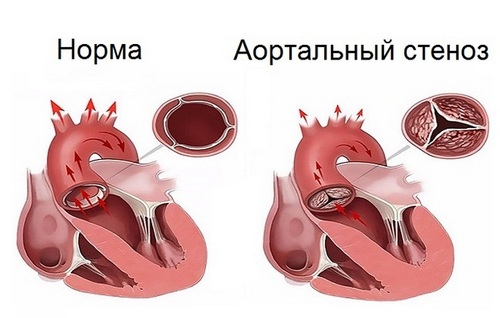

Фотографии и информация о приобретенных пороках сердца